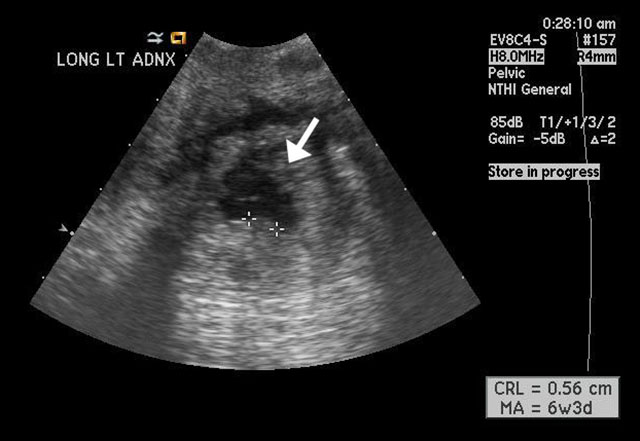

Figure 3

Magnified image shows the ectopic pregnancy in the left adnexa with the arrow pointing towards a fluid filled gestational sac that is anechoic. The calipers are measuring a hyperechoic area within the gestational sac, which most likely represents a fetal pole. |